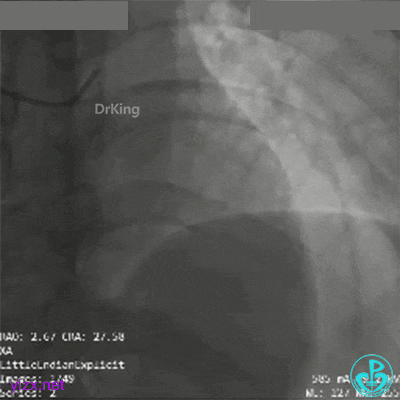

2.5×15mm球囊扩张后,替罗非班注射,显示残余狭窄合并血栓负荷。

患者出现血压下降、心动过缓,躁动,呕吐。